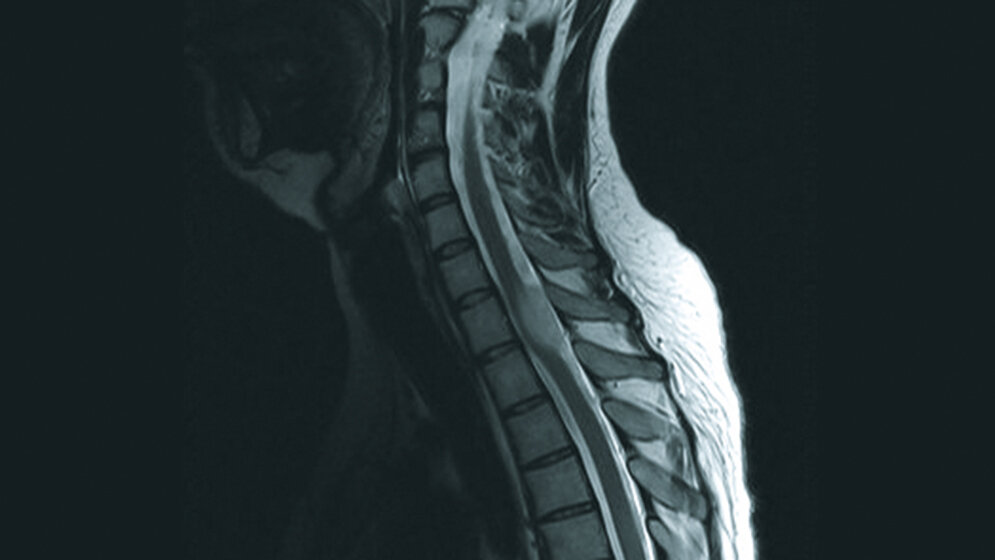

Tumoröse Veränderungen: Spinales Astrozytom

Die Behandlung und Prognose der spinalen Tumoren hängt zu einem großen Teil von der Histologie ab. Um residuale neurologische Defizite so gering wie möglich zu halten, ist eine frühzeitige Diagnose und Therapie neoplastischer und demyelinisierender Myelonveränderungen wichtig. Ein MRT der Neuroachse sollte in Fällen eines Hydrozephalus ohne entsprechende Veränderung durchgeführt werden. Für Radiologen und Neurochirurgen ist es wichtig, nicht-tumoröse und neoplastische Prozesse des Rückenmarkes zu erkennen und zu differenzieren.